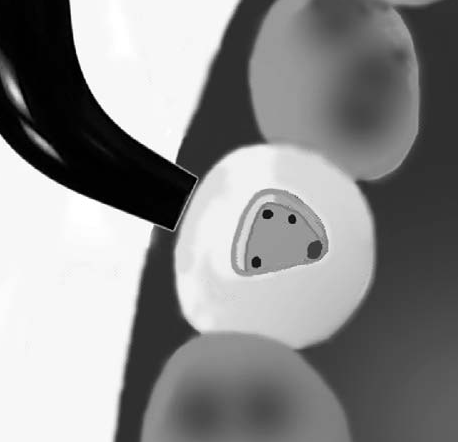

Como método

para ubicar los orificios de entrada de los conductos

solemos utilizar la transiluminación dentaria.

El conducto

y el orificio es

esencialmente

un agujero en

la raíz,

la

transmisión de luz

muestra

al orificio de entrada del conducto como una mancha

oscura en un fondo brillante. Ver imagen izquierda

superior,

la siguiente imagen es el resultado de utilizar una

cámara intraoral, con 10 aumentos (X10)

|

| En la

imagen derecha se observa el dispositivo de

transiluminación dentaria |